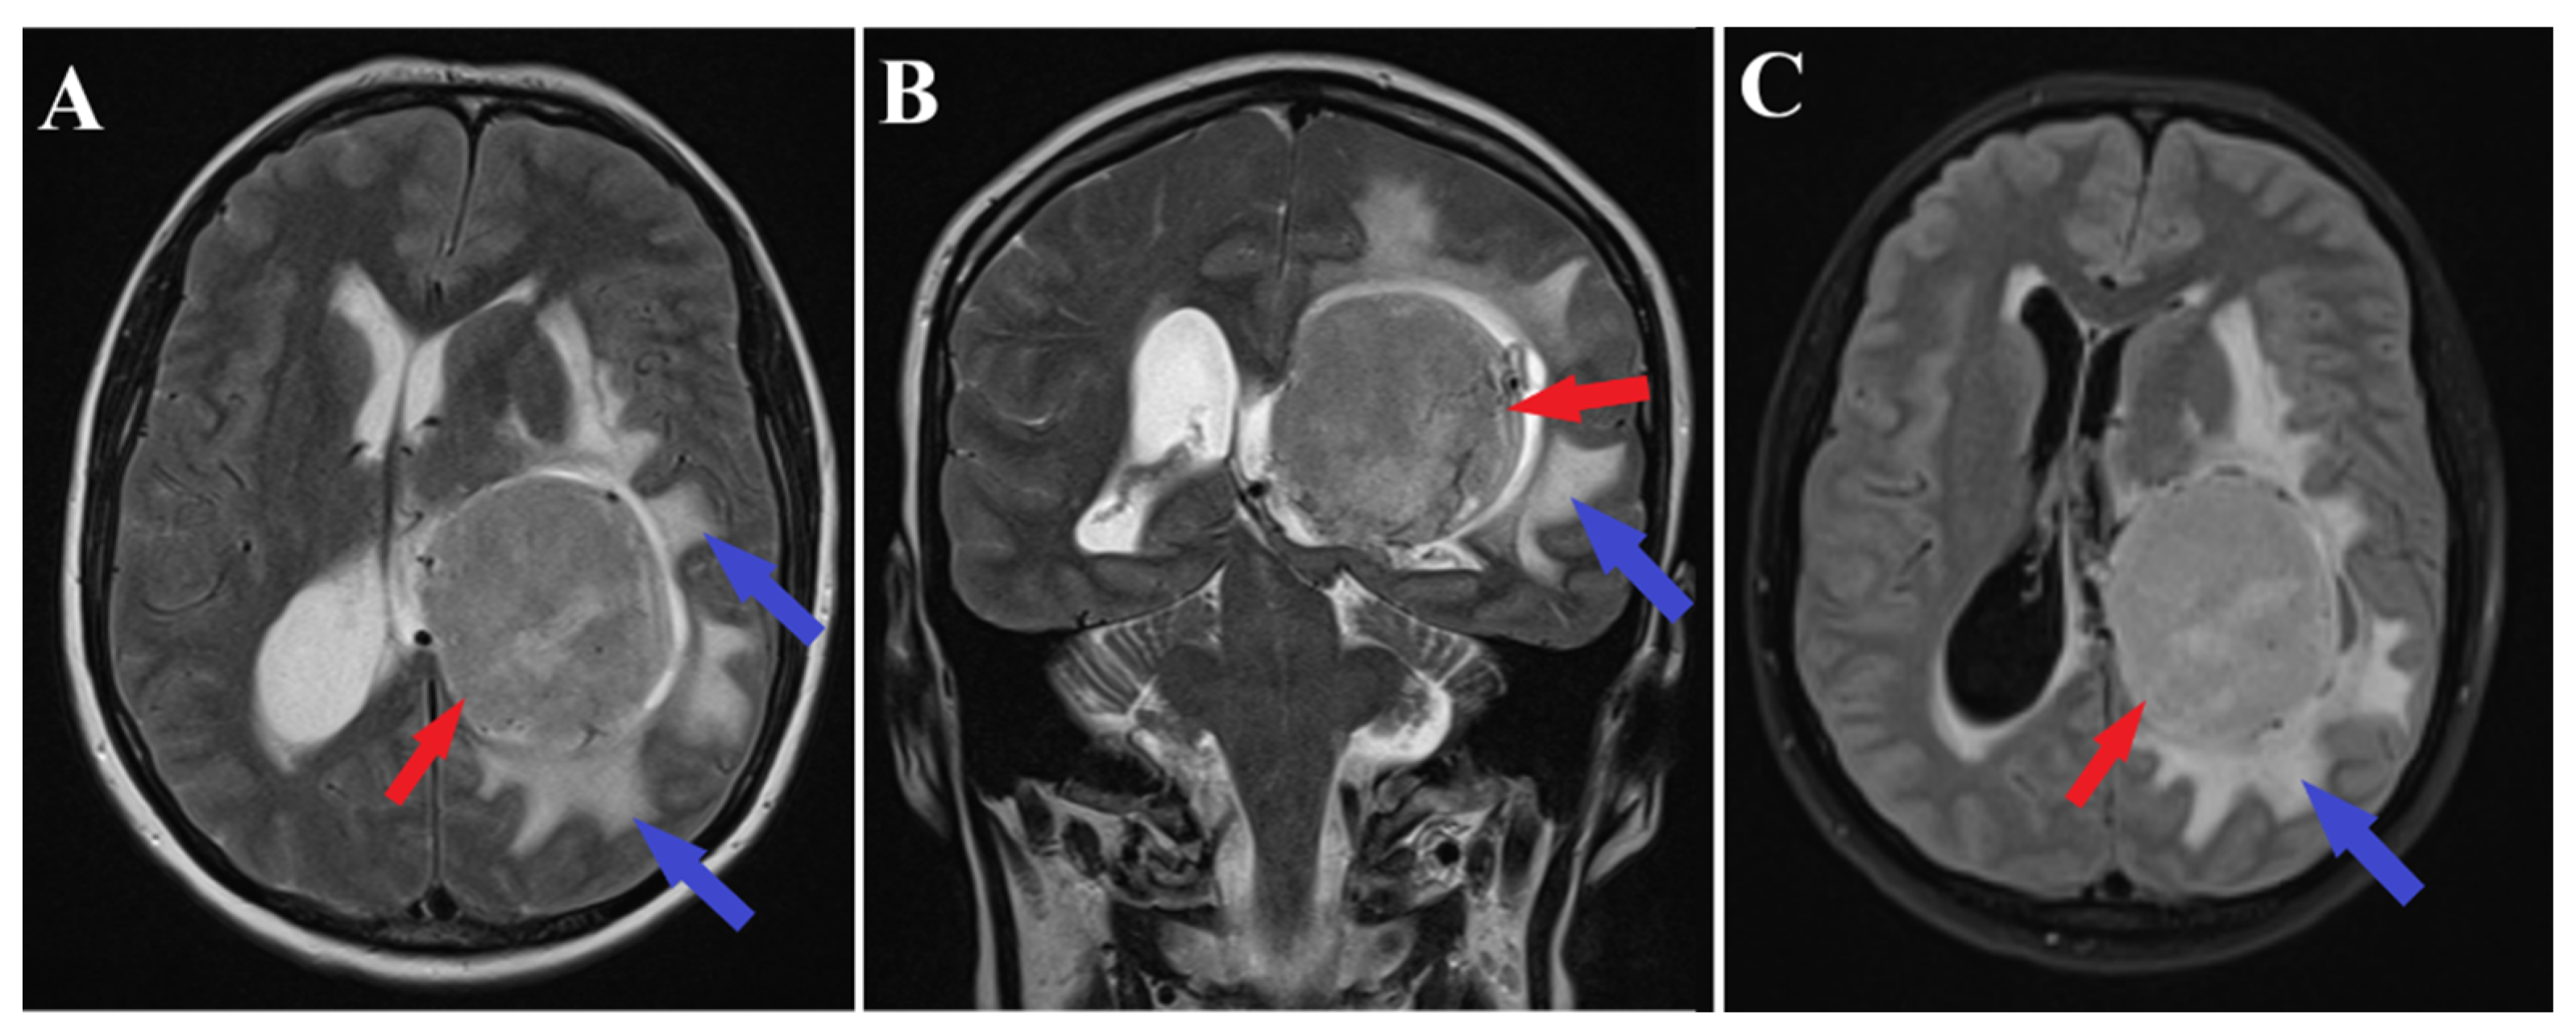

A brain MRI (i.e., multi-planar, multi-sequential brain MRI examination was performed on a General Electric 3T Signa Architect, Chicago, IL, USA) with contrast enhancement revealed an intraventricular tumor located in the body of the left lateral ventricle. The tumor presented as an ovoid, well-delineated mass with T1 hypointensity and T2 hyperintensity, measuring up to 60 mm in maximum diameter. It induced deformation of the left lateral ventricle. The tumor was associated with substantial digitiform edema, causing a shift in the midline structures and a potential risk of subfalcine herniation (Figure 1 and Figure 2).

Figure 2.

Preoperative MRI T2 and T2 FLAIR sequence. Axial section of MRI T2 sequence (A), coronal section of MRI T2 sequence (B) and axial section of T2 FLAIR sequence (C) are shown. Arrows indicate the intraventricular meningioma (red arrows) and significant digitiform edema (blue arrows).